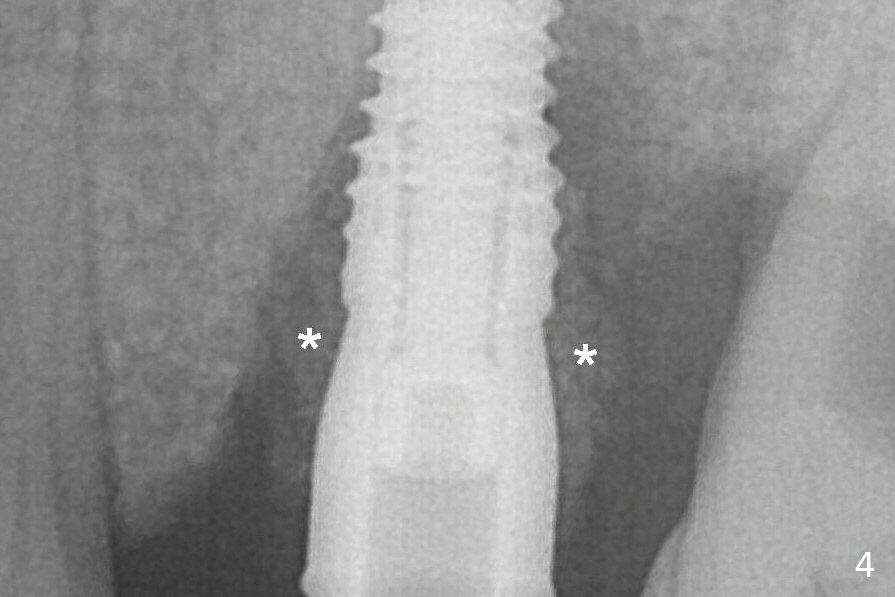

Bone Graft (Fig.4 *) is shown around the implant and a longer abutment (4.5x5.5(5) mm) after trimming.  The graft cannot be pushed to the mesial surface of the tooth #14, probably due to the presence of the interdental papilla.